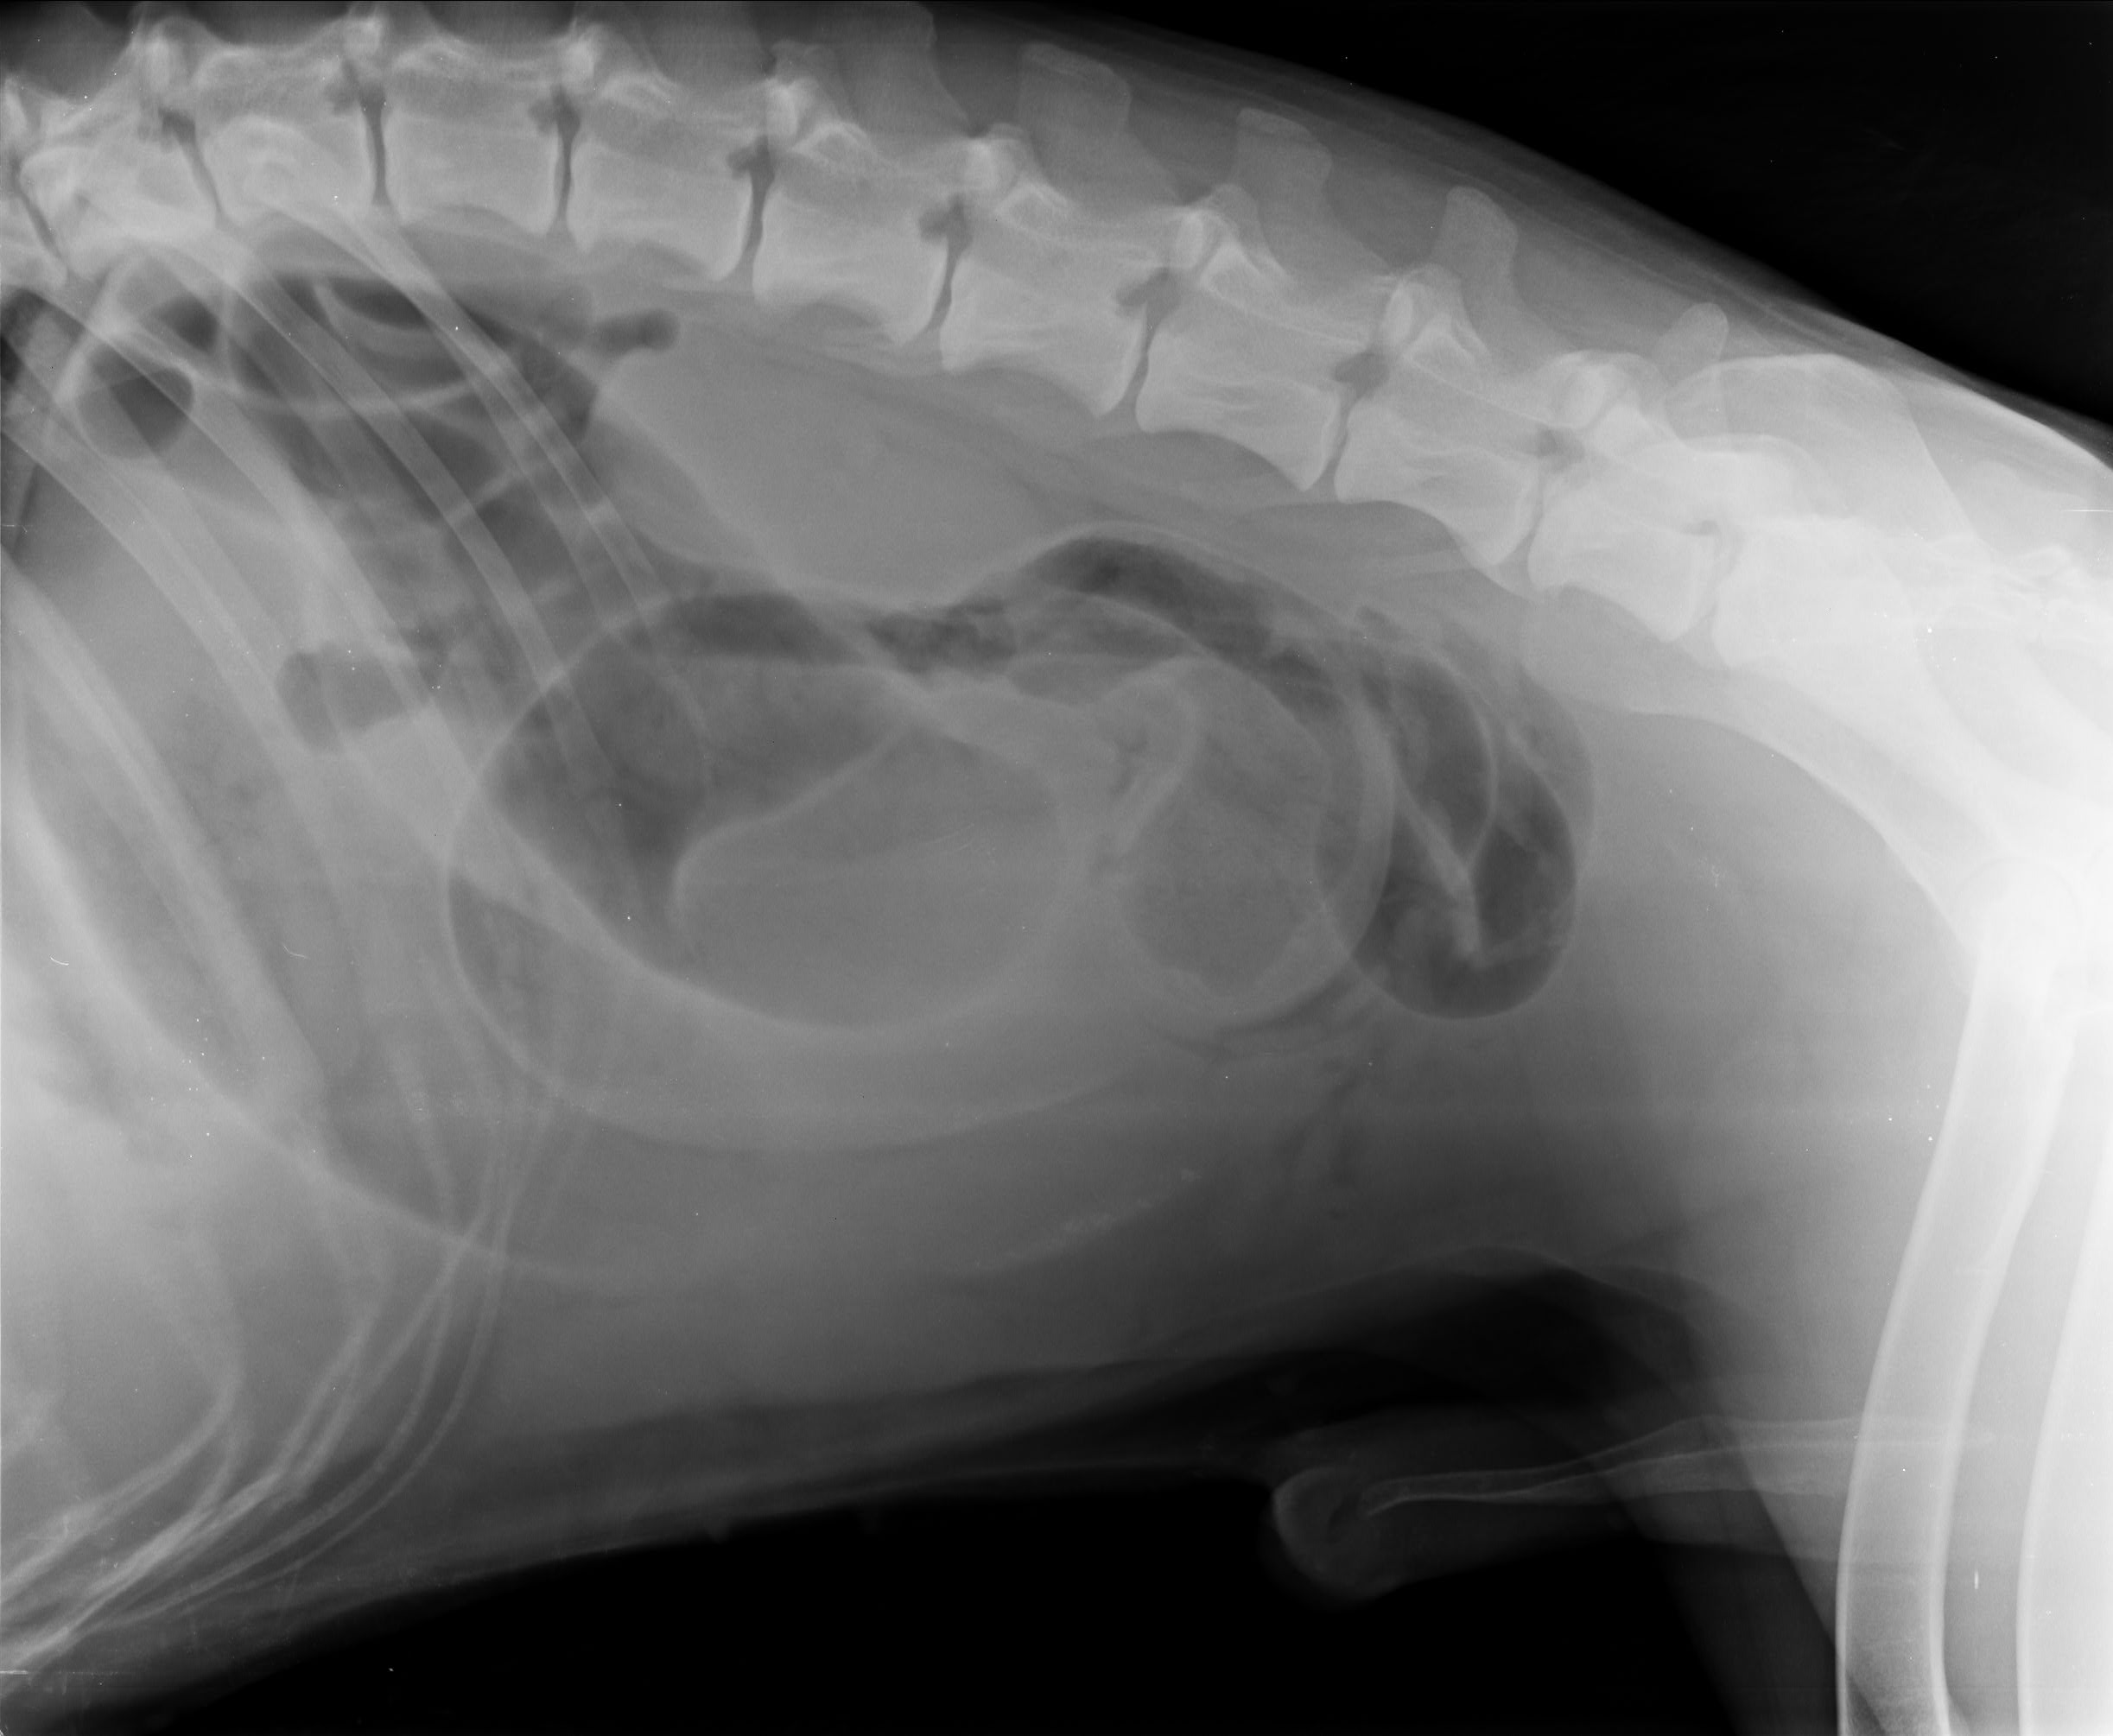

nisam siguran da sam takvu sliku rendgena gledao na monitoru u ambulanti Lonjica, ali nigdje nema moga imena ili imena moga psa

drugi rtg

Goran u tijeku razgovora indirektno potvrđuje da ultrazvuk koji se navodi u nalazu nije rađen 13.4.2021., već kao kad je pas bio pod anestezijom ili eutaniziran jer spominje da su radili Zrinka i on. To je dokaz lažiranog nalaza i da je pas podvrgnut operaciji na osnovu rendgena, a ne ultrazvuka ili laparoskopije. U dijelu gdje Goran kaže da nemaju nalaz ultrazvuka jer se gleda na monitoru, ali da se na rendgenu bolje vidi, a Zrinka to prije operacije nije vidjela, znači samo jedno, da svatko vidi drugačije ili da to nisu rendgenske snimke moga psa, da su mi i to podvalili.

Na rendgen snimkama nema moga imenam prezimena ili imena moga psa.